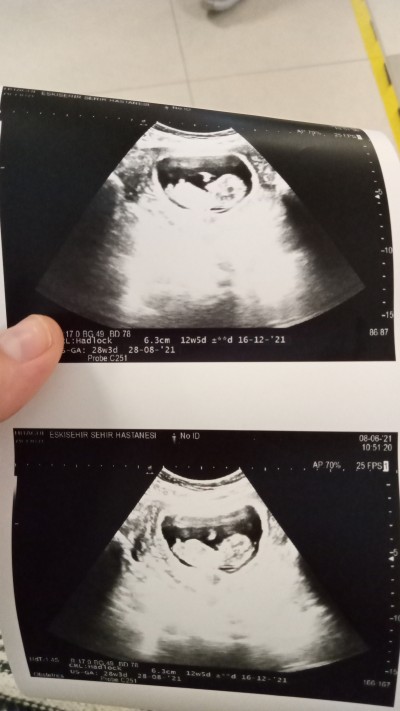

Arkadaşlar 12+5 gunluk hamileyim cinsiyet tahmini yapabilirmisiniz doktorum 2 hafta sonra soylicem dedi

Gebelik haftası 12+5